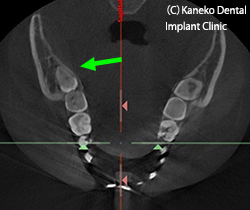

2)親知らずの抜歯へのCTの利用

3D画像より、患者さんにわかりやすく、

親知らずの位置を説明できます。矢印が親知らずです。

MPR像(CTの断面2D画像)より、下顎管との距離、歯根の数、歯軸の頰舌方向への振れぐあいを事前に知ることができ、抜歯術の難易度がわかります。